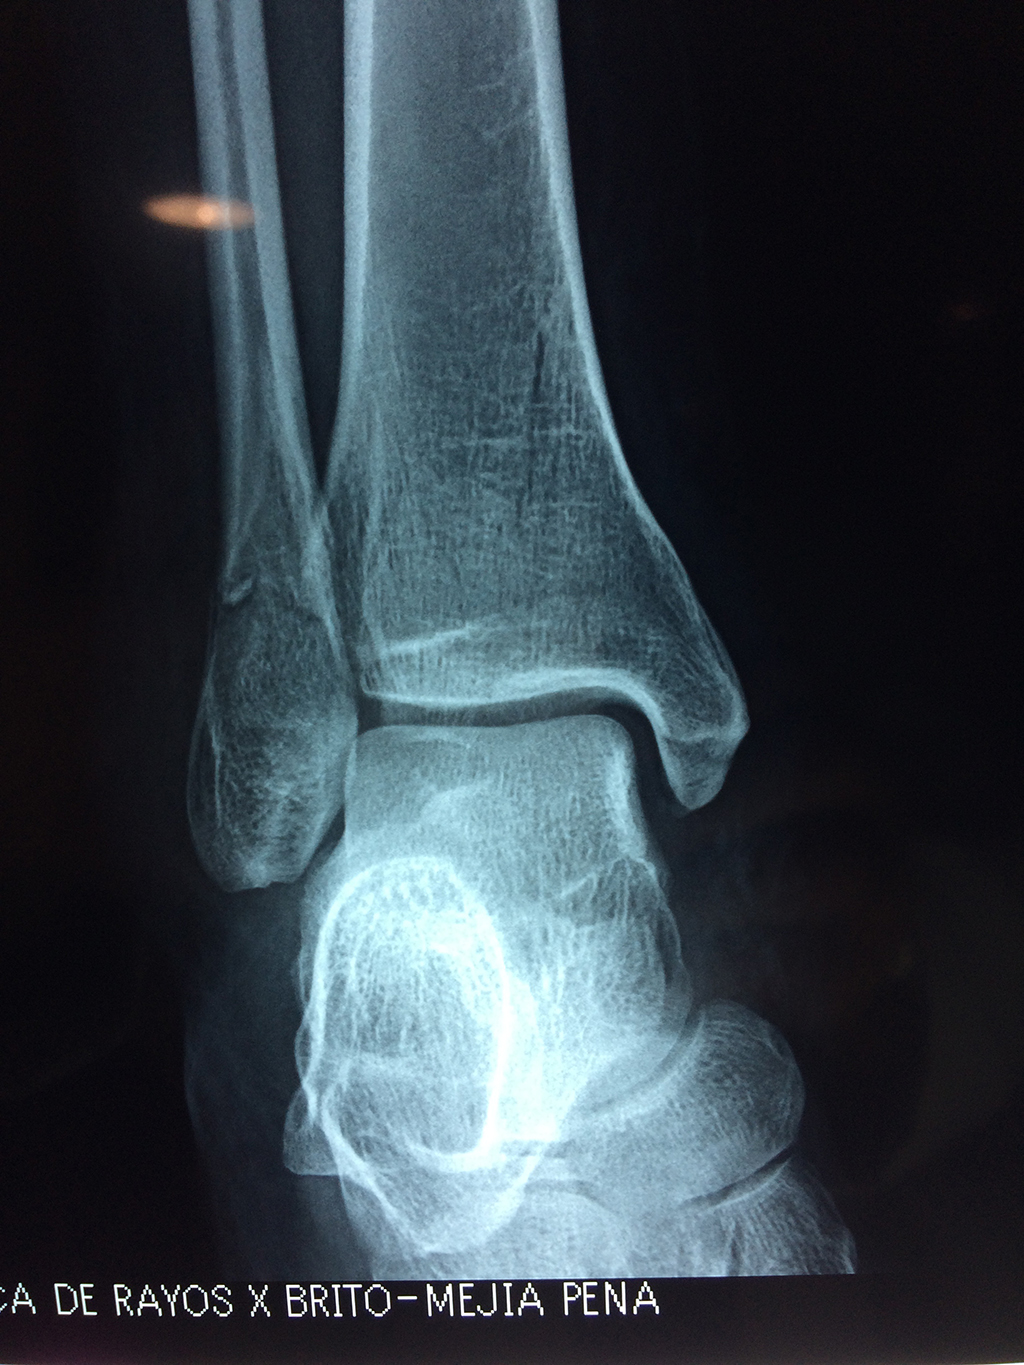

Una fractura de tobillo es la rotura de uno o más de los huesos del tobillo. Estas fracturas pueden ser:

Algunas fracturas de tobillo pueden requerir cirugía si:

- Los extremos de los huesos están desalineados entre sí (desplazados).

- La fractura se extiende hasta la articulación del tobillo (fractura intra-articular).

- Los tendones o ligamentos (tejidos que sujetan los músculos y los huesos entre sí) están rotos.

Cuando se necesita cirugía, es probable que esta implique el uso de clavijas de metal, tornillos o placas para sostener los huesos en su lugar mientras la fractura se consolida. Los elementos de soporte pueden ser temporales o permanentes.